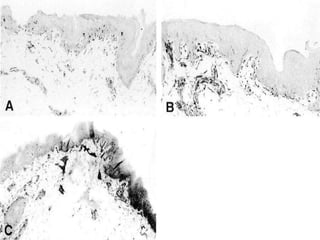

macrophage infiltrates

(A) CD68 immunoenzymatic reactivity of NL skin.

(B) PL skin.

(C)Epidermal CD68 expression pattern in PL skin

using high antibody concentration.

Immunoreactivity

(A)NKI-beteb (blue)/HLA-DR (red) double-label immunoreactivity showing

HLA-DR immunoreactivity of one remaining melanocyte (arrow) in PL

skin.

(B) NKI-beteb (red)/CD68 (blue) double-label immunoreactivity of normal

control (NC) skin showing CD68+ melanocytes (arrows).

C to F, Serial sections of PL vitiligo skin.

(C), NKI-beteb (blue)/CD8 (red) double-label immunoreactivity; long arrow,

CD8+ T cell apposed to melanocyte; short arrows, CD8+ T cells apposed to

melanocytic remnants.

(D) CD3 (red)/CLA (blue) double-label immunoreactivity showing a cluster of

double-immunoreactive T cells (arrows) at the epidermal/dermal

junction and CD3 single-immunoreactive cells in the dermal compartment

(asterisks).

(E) Granzyme-B

(F) perforin immunoreactivity in cells at the PL epidermal/dermal junction.